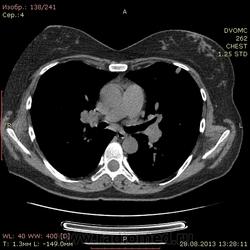

1961 г.р. В течение около 2х недель мучает сильный кашель, температура не поднималась, терапевны назначали антибиотики. Пропила неделю - без какого либо улучшения. Около полутора недель назад делали флюшку - без инфильтративных, корни немного расширены, структурны. Снгодня на флюшке появилась округлая тень слева. Решили сделать КТ - и вот результат.

Множественные мягкотканные мелкие узелки, лимфоаденопатия. Туберкалез? Саркоидоз? Mts? Не знаю чего и думать...прошу помощи.

1. Внутригрудная лимфоаденопатия. 2.Участки снижения пневматизации легочной ткани по типу "матового стекла". 3. Наличие в обоих легких узелковых образований (гранулем), преимущественно прилежащих к костальной, междолевой и межсегментарной плевре. Комплекс симптомов, наиболее характерен для Саркоидоза легких и ВГЛУ. Показано гистологическое подтверждение: трансбронхиальная внутрилегочная биопсия (информативность до 80% или медиастиноскоия и медистинотомия (информативность до 95%).

Лимфапролиферативное заболевание (ЛГМ, лимфома) vs саркоидоз. Нет тут туберкулеза.

На туберкулез легких не похоже.Лимфаденопатия. Метастазы. В меньшей степени вероятен саркоидоз.